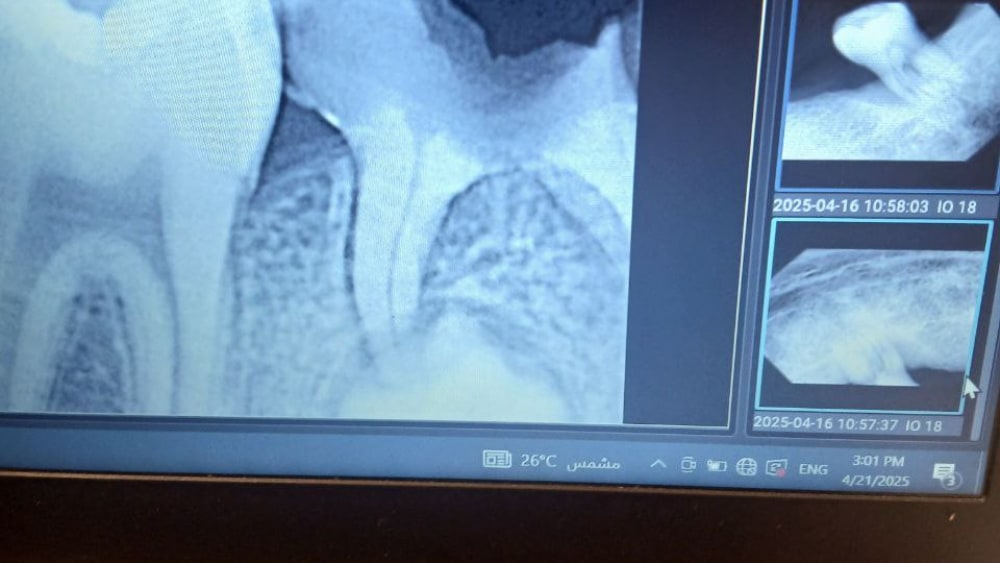

Caries in a MIH case

Patient Presented to the operative clinic at Ain shams university complaining of sudden pain in her lower teeth. Upon examination caries were found related to her lower right 6 & it was also suspected that the patient suffers from MIH judging from the caries pattern she presented with.